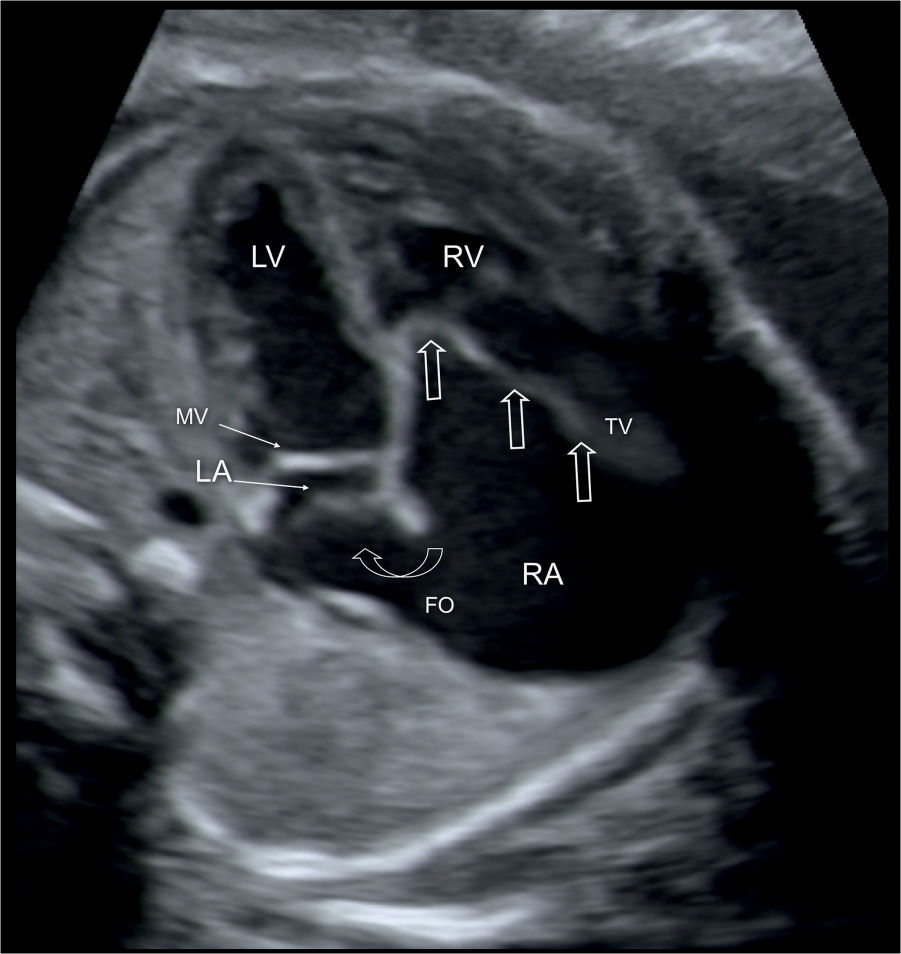

From obgynkey.com

Ebstein Anomaly, Tricuspid Valve Dysplasia, and Tricuspid Regurgitation Ebstein Anomaly It affects the tricuspid valve in your heart and can cause an enlarged heart, irregular heartbeat and heart failure. Ebstein anomaly is a rare congenital cardiac defect that consists of variable apical displacement from the annulus and dysplasia of the septal and. This means it's a congenital heart defect. The severity of the defect varies widely. The tricuspid valve is. Ebstein Anomaly.

Ebstein Anomaly, Tricuspid Valve Dysplasia, and Tricuspid Regurgitation Ebstein Anomaly Ebstein’s anomaly is a rare birth defect. This means it's a congenital heart defect. The severity of the defect varies widely. Ebstein anomaly is a rare congenital heart disease characterized by apical. It affects the tricuspid valve in your heart and can cause an enlarged heart, irregular heartbeat and heart failure. The tricuspid valve is incorrectly formed. Ebstein anomaly is. Ebstein Anomaly.

Ebstein Anomaly, Tricuspid Valve Dysplasia, and Tricuspid Regurgitation Ebstein Anomaly It affects the tricuspid valve in your heart and can cause an enlarged heart, irregular heartbeat and heart failure. The severity of the defect varies widely. This means it's a congenital heart defect. Ebstein’s anomaly is a rare birth defect. Ebstein anomaly is a rare congenital cardiac defect that consists of variable apical displacement from the annulus and dysplasia of. Ebstein Anomaly.

Ebstein Anomaly, Tricuspid Valve Dysplasia, and Tricuspid Regurgitation Ebstein Anomaly Ebstein anomaly is a rare congenital heart disease characterized by apical. Ebstein anomaly is a rare heart problem present at birth. The severity of the defect varies widely. Ebstein anomaly is an uncommon congenital cardiac anomaly, characterized by a variable developmental anomaly of the tricuspid. The tricuspid valve is incorrectly formed. This means it's a congenital heart defect. Ebstein anomaly. Ebstein Anomaly.